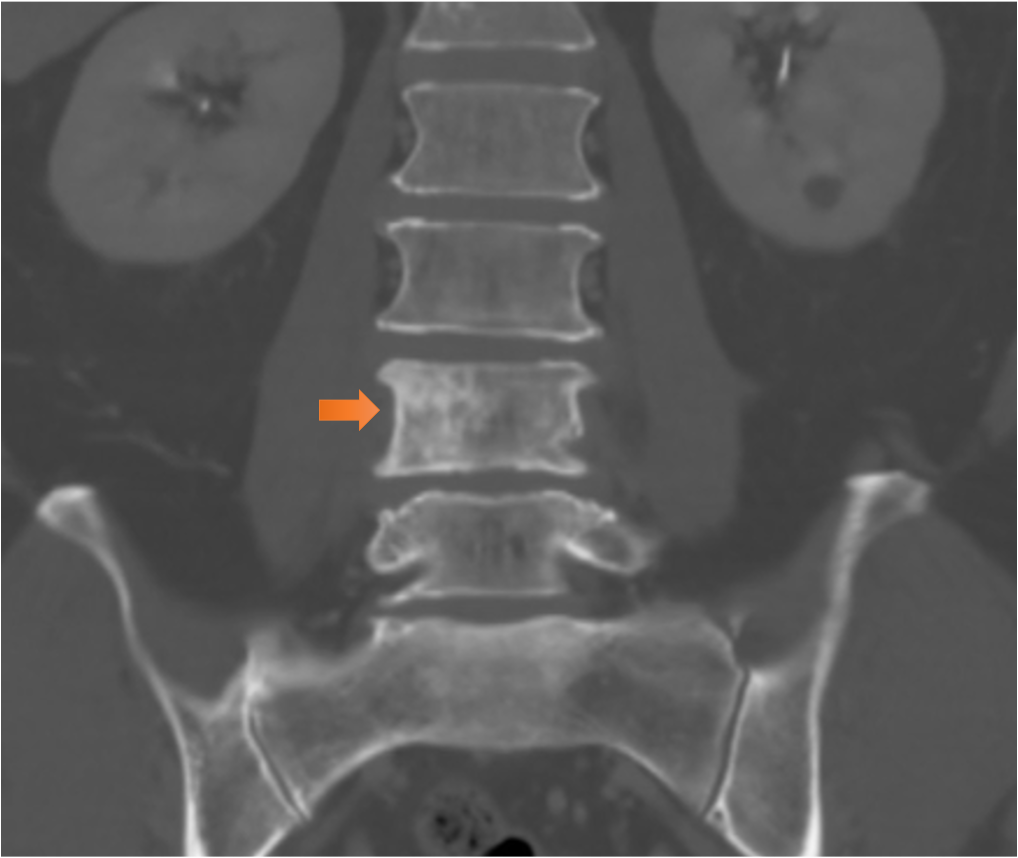

図8.骨転移

L4に不整な造骨性変化を認めた。脊柱管内への進展は認めず。